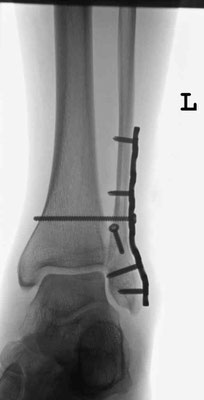

Der Außenknöchel wird dann in Narkose über einen 10 -13 cm langen Hautschnitt eingerichtet und mit einer Schrauben und einer Platte fixiert. Danach zentriert sich das Sprunggelenk meistens schon sehr gut, ein gerissenes Innenband muss in diesem Fall nicht genäht werden. Es heilt von selbst. Ist der Innenknöchel ebenfalls gebrochen, wird dieser im nächsten Schritt über einen kleinen Schnitt freigelegt, eingerichtet und mit Schrauben stabilisiert. Den hinteren Knöchel kann man dann in der Regel mit einer Schraube von vorne fassen und in seine Position ziehen. Nicht selten reißt die Bandverbindung zwischen Wadenbein und Schienbein (Syndesmose). In diesen Fällen wird nach Naht des Bandes zur Sicherung eine sog. Stellschraube eingebracht. Diese verbindet Waden- und Schienbein bis das Band geheilt ist und wird dann nach 6 Wochen in lokaler Betäubung wieder entfernt.

Ist der Außenknöchel mehrfach gebrochen oder ist der Knochen relativ weich, werden winkelstabile Platten verwendet. Zertrümmerungen der Gelenkfläche (Pilon tibiale) führen in kürzester Zeit zu einer massiven Schwellung. In diesen Fällen wird der Fuß zunächst mit einem Außenspanner (Fixateur externe) ruhiggestellt, bis er soweit abgeschwollen ist, das man offen operieren kann.